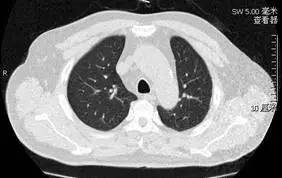

诊治体会:患者老年男性,慢性病程,主要表现为咳嗽、活动后气短,胸部 CT(图 1)

图 1: 治疗前胸部 CT

主要表现为磨玻璃样渗出,且上肺较下肺明显,无发热表现。入院初期我们考虑最多的是弥漫性实质性肺疾病,根据上述特点,过敏性肺炎是我们最先考虑的疾病,同时需要和其他类型的间质性肺疾病及感染性疾病进行鉴别。行气管镜检查,肺泡灌洗液(BALF)细胞计数分类不符合过敏性肺炎特点(中性粒细胞为主,而不是淋巴细胞为主),经支气管镜肺活检(TBLB)病理结果也未见典型肉芽肿样改变,因此,过敏性肺炎诊断依据不足。同时没有风湿病相关症状体征,免疫相关检查均为阴性,因此除外结缔组织病继发肺部病变可能。没有结核中毒症状,BALF 和痰涂片抗酸染色及核酸检测阴性,PPD、T-spot-TB 阴性,因此除外肺结核。病毒及支原体、衣原体、军团菌下呼吸道分泌物核酸检测阴性,除外病毒及非典型病原体感染。痰脱落细胞、肺组织病理、血肿瘤标记物检测阴性,除外恶性肿瘤。

正当我们一筹莫展的之际,肺泡灌洗液培养回报:肺炎克雷伯菌。是致病菌吗?这是我们拿到结果后面临的第一个问题。患者无发热,胸部 CT 表现为磨玻璃影(图 1),不像典型的细菌性肺炎。患者每日咳出的砖红色胶冻样痰(图 2)是再次吸引我们的注意力,反复多次留取痰标本涂片均提示革兰氏阴性杆菌,似乎与肺泡灌洗液培养吻合。